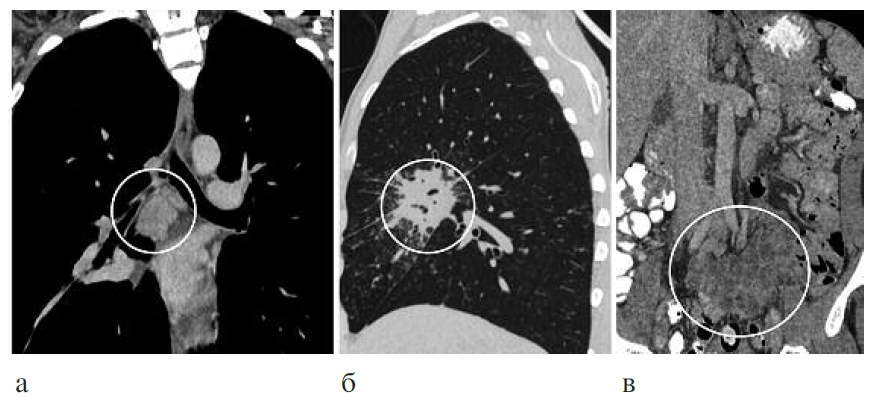

Клинический диагноз: ВИЧ-инфекция, 4В стадия, фаза прогрессирования вне АРТ. Генерализованный туберкулез: туберкулез внутригрудных лимфатических узлов, правого главного, промежуточного и среднедолевого бронхов, диссеминированный туберкулез легких, правосторонний экссудативный плеврит, туберкулез внутрибрюшных и забрюшинных лимфатических узлов, туберкулез периферических лимфатических узлов, МБТ+, ШЛУ, распространенный висцеральный кандидоз, манифестная цитомегаловирусная инфекция, хронический вирусный гепатит С, наркомания. Уровень CD4+ лимфоцитов 186 кл/мкл, вирусная нагрузка более 1 млн копий/мл, в мокроте ДНК МБТ с лекарственной устойчивостью к рифампицину. Начата противотуберкулезная химиотерапия по IV режиму. Переносимость лечения неудовлетворительная (гепатотоксическая реакция). При рентгенологическом обследовании отмечено объемное уменьшение правого легкого, в верхней доле на фоне фиброза полость распада размером 3,8¥2,2 см с толстыми неровными стенками, очаги диссеминации в обоих легких (рис. 3). В течение первого месяца лечения отрицательная клиническая динамика, получен результат посева мокроты, выявлена ШЛУ МБТ к изониазиду, рифампицину, стрептомицину, канамицину, каприомицину, офлоксацину. Назначен V режим химиотерапии с включением линезолида, бедаквилина, азитромицина, моксифлоксацина, протионамида, теризидона, этамбутола. Через 2 мес лечения присоединена АРТ. Через 6 мес терапии по новому режиму отмечены прекращение бактериовыделения и выраженная положительная клинико-рентгенологическая динамика (рис. 4). Больной выписан для продолжения лечения в амбулаторных условиях, в последующем в течение 2 лет рецидива туберкулеза не отмечено. Данное наблюдение показывает возможность эффективного лечения больного коинфекцией ВИЧ/туберкулез с использованием новых режимов химиотерапии.

Рис. 4. КТ-исследование через 6 мес лечения: а – регресс изменений во внутригрудных лимфатических узлах; б – рассасывание инфильтративных и очаговых изменений в легочной ткани.